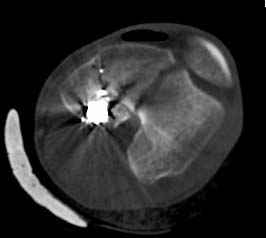

У молодого человека огнестрельное слепое ранение н/3 правого бедра. Поступил в клинику с внутрисуставным многооскольчатым Т-отразным переломом дистального отдела бедренной кости. Дополнительно на  СТ-исследовании обнаружен перелом внутреннего мыщелка Hoffa со смещением.<br><br>

Больной взят в операционную на второй день, где из небольшого медиального доступа выполнена артротомия коленного сустава. Произведена репозиция отломков, фиксация винтами. Попутно удалена пуля. Первым делом была достигнута репозиция медиального мыщелка (перелома Hoffa, где коронарная плоскость перелома трудно поддается закрытой репозиции и фиксации. ) Затем была достигнута идеальная репозиция суставной поверхности бедра и фиксация компрессирующими headless  screws.<br><br>

Дистальный отдел бедра был дополнительно фиксирован buttress пластиной с медиальной стороны из того же разреза. Для усиления фиксации латеральной колонны -  с латеральной стороны закрытым способом из минидоступа установлена еще buttress plate.  Пулевой канал дополнительно не подвергался хирургической обработке.<br><br>